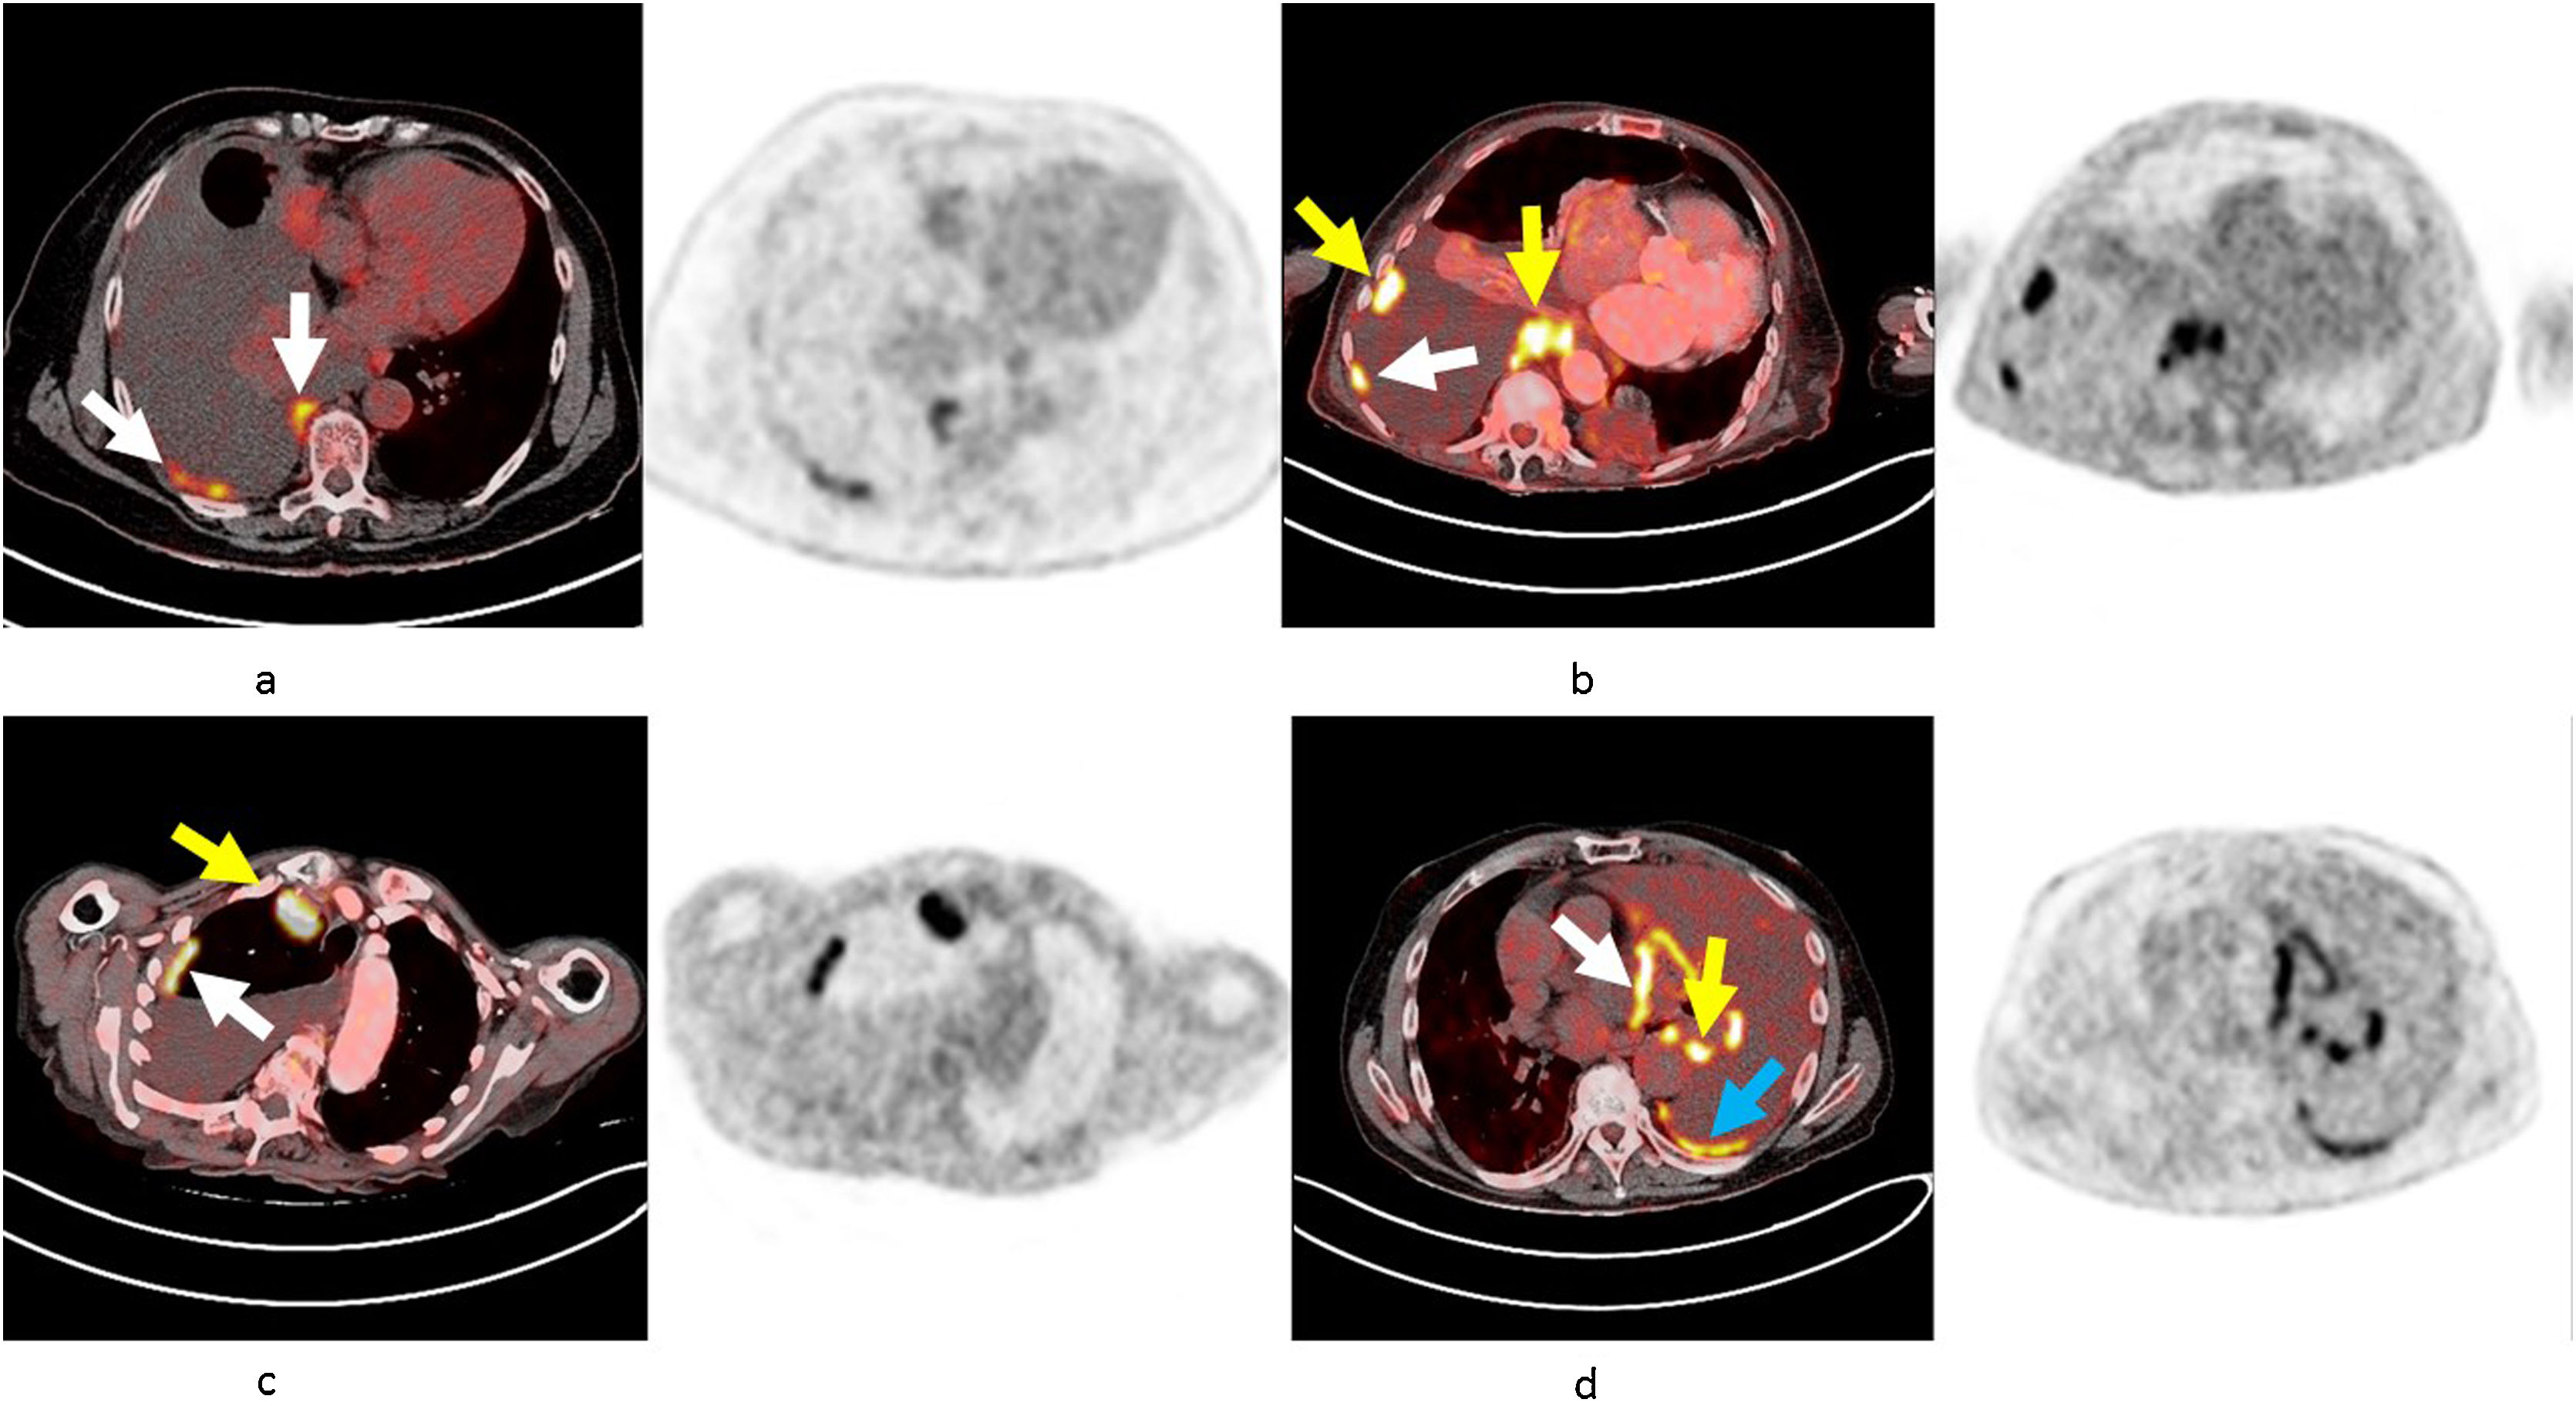

ResultsOne hundred and ninety-nine patients were enrolled in the referral cohort (91 with malignant effusions and 108 benign). The most useful parameters for the development of a PET-CT score were: nodular pleural thickening, pleural nodules with SUV>7.5, lung mass or extra pleural malignancy (10 points each), mammary lymph node with SUV>4.5 (5 points) and cardiomegaly (−1 point). With a cut-off value of >9 points in the referral cohort, the score established the diagnosis of malignant pleural effusion with sensitivity 87.9%, specificity 90.7%, positive predictive value 88.9%, negative predictive value 89.9%, positive likelihood ratio 7.81 and negative likelihood ratio 0.106. These results were validated in an independent prospective cohort of 75 patients.